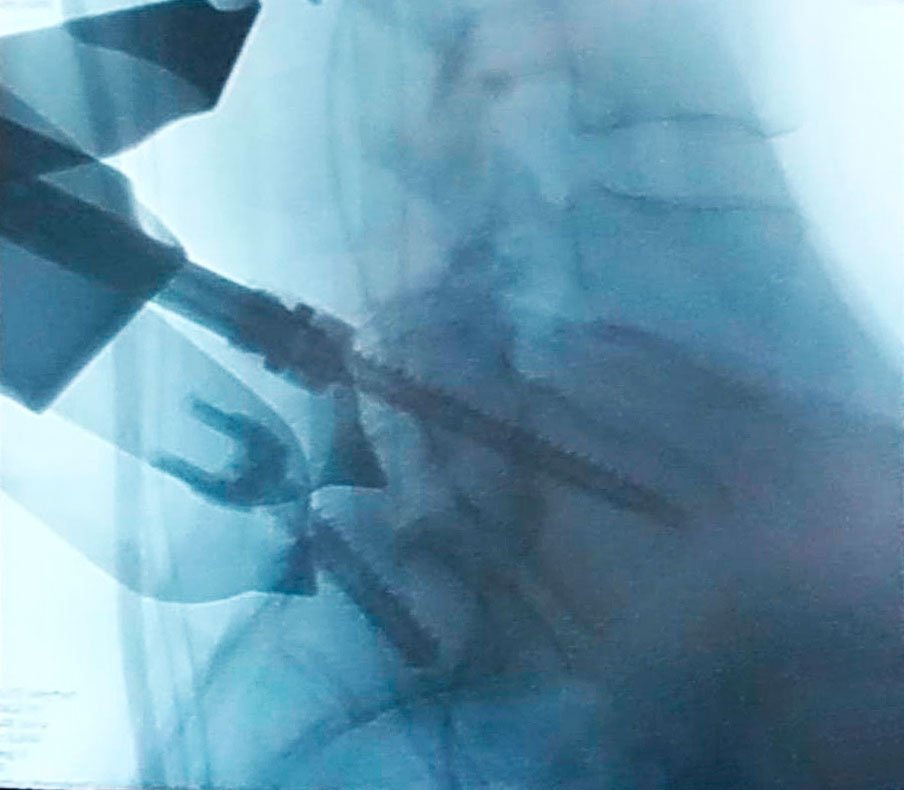

FIJACIÓN TORACOLUMBAR

Cirugía Fusión Espinal.

La fusión espinal es una cirugía que permite conectar dos o más segmentos vertebrales en cualquier parte de la columna vertebral. A este procedimiento se le conoce cómo artrodesis espinal. Este procedimiento está diseñado para el tratamiento de inestabilidad de la columna, la enfermedad degenerativa del disco, espondilolistesis, estenosis degenerativa, deformidades como la escoliosis y la cifosis y fracturas.